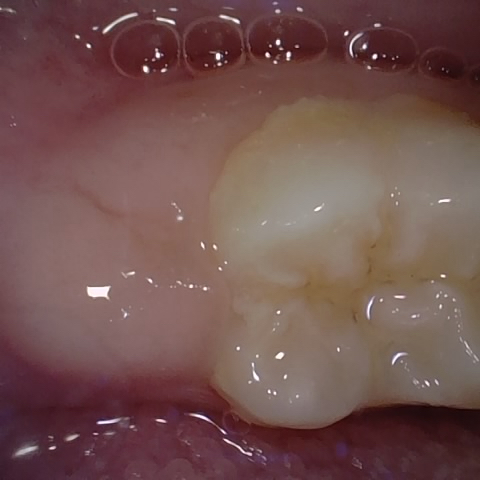

Annotated as "Bad"